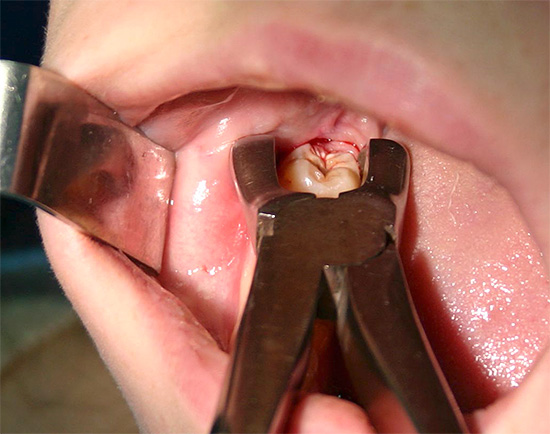

In quali casi potresti dover separarti da un dente?

Come accennato in precedenza, la difficile eruzione del dente del giudizio (pericoronite) è la prima indicazione per l'estrazione del dente secondo il moderno approccio alla salute dentale. Certo, puoi sempre convincere il medico a farti solo una sezione del cappuccio gengivale, ma dov'è la garanzia che il dente "non si arrampichi storto", le sue radici non si intrecciano con le radici dei denti vicini, che il cappuccio non ricresce e l'infiammazione non continua di nuovo.

Con la pulpite, i denti dovrebbero sempre essere preservati, ma la parodontite è un argomento speciale. Le forme acute di parodontite sono più facili da trattare, il che non si può dire della possibilità di preservare i denti con le cisti. Tuttavia, anche la cisti della cisti è diversa, quindi, in ogni caso, vengono determinati la prognosi della malattia, la prospettiva del trattamento e l'importanza del dente nella dentatura e il morso nel suo insieme.

I processi purulenti pronunciati periostite, osteomielite, ascessi, flemmone e altri odontogeni (dal dente) spesso determinano le indicazioni per la rimozione. Se il dente si trova vicino alle radici infiammate o nel seno mascellare stesso, è quasi sempre una questione di rimuovere il dente per interrompere l'alimentazione del seno con l'infezione.